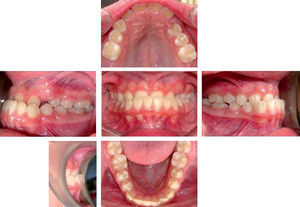

REPORTE DE CASO CLÍNICODiagnóstico y plan de tratamientoPaciente de 13 años de edad, género femenino, sin antecedentes médicos relevantes que acudió a la Clínica de Ortodoncia de la escuela de Odontología de la Universidad Autónoma de Guadalajara, refiriendo inconformidad tanto ella como su representante con su apariencia dental. La paciente describe un biotipo facial mesocefálico, tercio facial inferior ligeramente disminuido, pabellones auriculares con proyección asimétrica, ancho bucal coincidente con la distancia inter-iris, competencia labial, labios gruesos, frente recta, tabique nasal recto, perfil ligeramente cóncavo, distancia cérvico-mental en norma, línea estética en rango aceptable, labio inferior ligeramente evertido por delante de la línea estética facial, competencia labial y buen desarrollo malar (Figura 1).

En el análisis intraoral presentaba mordida cruzada y profunda anterior, línea media inferior desviada con respecto a la superior 2mm a la izquierda, overbite de 5mm, overjet de 3mm, relación molar clase I derecha e izquierda, clase canina indeterminada bilateral, arco superior ovoide, ausencia de los caninos permanentes y temporales (pérdida significativa de longitud de arco), arcada inferior ovoide, apiñamiento leve y 3mm de curva de spee (Figura 2).